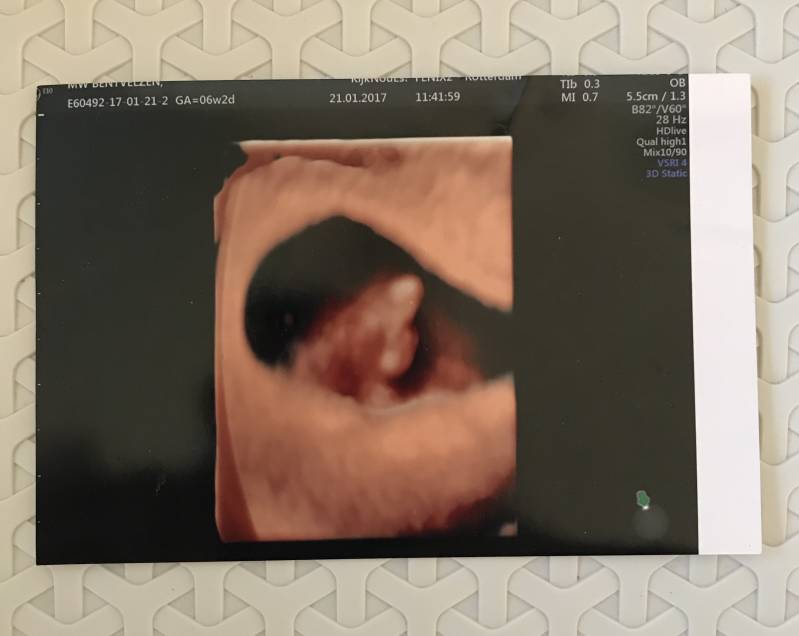

Op 21 Januari hadden we dan eindelijk de eerste echo! De afspraak was in echopraktijk Kijk nou es!* in Rotterdam. Wij hebben voor deze locatie gekozen omdat ze daar al vanaf 6wk een echo inplanden, en wij wilden natuurlijk zo snel mogelijk ons kindje zien. Kotsmisselijk kwam ik daar aan, ook door de zenuwen, en we moesten even wachten voordat we geholpen werden. Toen ik eenmaal op de onderzoeksbank lag en de echo werd gemaakt, zagen wij daar een piepklein balletje, en als je goed keek zag je zelfs het hartje kloppen! Het zag er allemaal goed uit, en wij gingen zielsgelukkig weer naar huis. Het was een kindje! Een kloppend hartje! Toen konden we gaan bedenken hoe wij dit iedereen gingen vertellen, en wanneer!